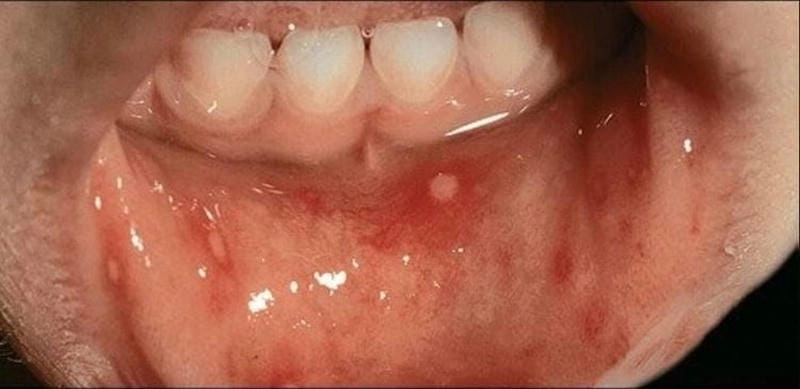

Những hình ảnh bệnh tay chân miệng cấp độ 1 đầu tiên có thể khiến nhiều người chủ quan vì triệu chứng nhìn qua tưởng chỉ là vết muỗi đốt. Nhưng đằng sau đó là nguy cơ lây lan nhanh, nhất là ở trẻ nhỏ. Từ các nốt hồng ban li ti ở lòng bàn tay, bàn chân cho tới vài mụn nước nhỏ ở quanh miệng – tất cả đều là dấu hiệu sớm cần nhận biết. Việc nhìn rõ những hình ảnh ở giai đoạn đầu là cách cảnh báo sớm, ngăn bệnh tiến triển sang cấp độ nguy hiểm hơn.

Tổng hợp ảnh tay chân miệng cấp độ 1 mang đến cái nhìn chân thực, không hề che giấu về diễn biến ban đầu của căn bệnh tưởng chừng vô hại này. Qua loạt ảnh cận cảnh, bạn sẽ thấy rõ các nốt mụn li ti xuất hiện rải rác nhưng có quy luật, tập trung ở những vùng dễ bị bỏ qua. Đừng xem thường – chỉ một vài nốt nhỏ có thể là dấu hiệu của cơn bùng phát sắp tới. Đây chính là kho tư liệu quý giá cho phụ huynh và nhân viên y tế nhận diện sớm và phản ứng kịp thời.